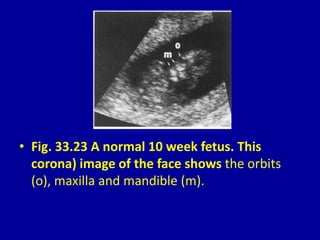

• Fig. 33.23 A normal 10 week fetus. This

corona) image of the face shows the orbits

(o), maxilla and mandible (m).

• Fig. 33.23A normal 10 week fetus. This corona) image of the face shows the orbits (o), maxilla and mandible (m).